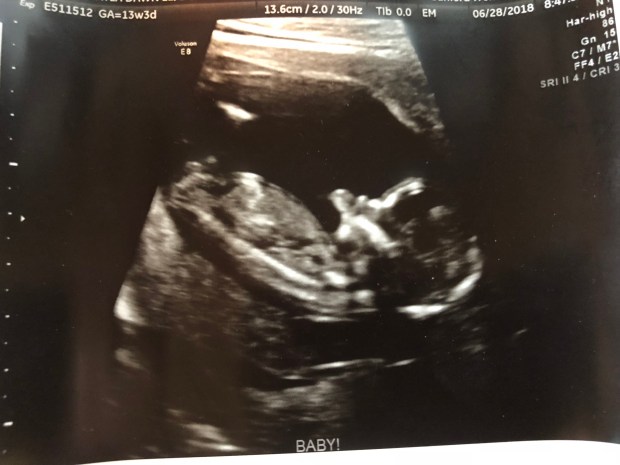

Then came the fun part, our 15-20 minutes looking at our baby!

But it was there instantly!  I didn’t need to search for the beautiful flicker because it showed up right on queue, plain as day, and lit up the screen for me!  Throughout the entire scan, it was almost all I could look at, that marvelous flickering organ!  Our baby continued to have a pulse and be alive and that was my biggest concern that day!

Baby was moving around like crazy.  They alway are moving around like crazy, at every scan we’ve had they are an active little bean!  What does this mean for the future?!?!

Speeding up now, everything came back stellar!  I had a follow up appointment with my OB this last Tuesday to review the results.  To be honest, it was more so that I could see & hear baby’s heartbeat again.  She had already shared the results with me via my online medical chart.  I just needed to see baby swimming around again and know that everything was still A-OK!